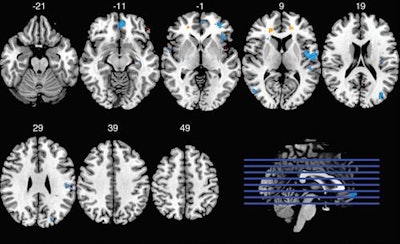

Unlike previous research on former athletes who showed signs of cognitive impairment, this neuroimaging study compared former players who had no symptoms of such deficiencies. The researchers used diffusion-tensor MR imaging (DTI-MRI) to analyze white-matter structural integrity and functional MRI (fMRI) to evaluate brain function while the players performed a memory task. They found early signs of brain changes that could be hallmarks of future problems.

Clark and colleagues found lower fractional anisotropy values in frontal white-matter tracts, indicating abnormal movement of water molecules in brain tissue. The deficiency was more prevalent in nonspeed players, such as offensive and defensive linemen, compared with speed positions, such as quarterbacks, running backs, wide receivers, linebackers, and defensive backs. Kickers were not included in the study.

The researchers found that former college players with more than three concussions had lower fractional anisotropy white-matter area than players with one or no concussions (p = 0.035).

Interestingly, the opposite was true for former professional players. Former athletes with one or no concussions had significantly lower fractional anisotropy than players with three or more concussions (p = 0.001). They also had significantly lower BOLD percent signal change across the three working memory tasks (p < 0.001).

As for the position comparisons, nonspeed players with more than three concussions had significantly lower fractional anisotropy in frontal white matter than players with no or one concussion (p = 0.002). There also were several frontoparietal regions with lower BOLD percent signal change among the nonspeed players with more concussions than the nonspeed players with fewer concussions.